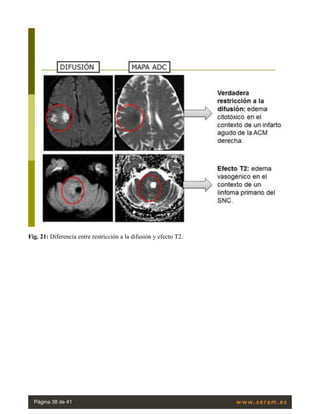

Fig. 21: Diferencia entre restricción a la difusión y efecto T2.

Podríamos decir que el mapa ADC constituye el “negativo” de la imagen de difusión: así, cuando existe

una verdadera restricción a la difusión lo veremos “blanco” en esta secuencia y “negro” en el mapa

ADC; en aquellos casos de efecto T2, aparecerá “blanco” en difusión y “blanco” en el mapa ADC (no

existe restricción al movimiento). De aquí se deriva la gran importancia de esta herramienta en casos

como el infarto subagudo ó los quistes simples, que emitirán una alta señal en la secuencia de difusión

por efecto T2.